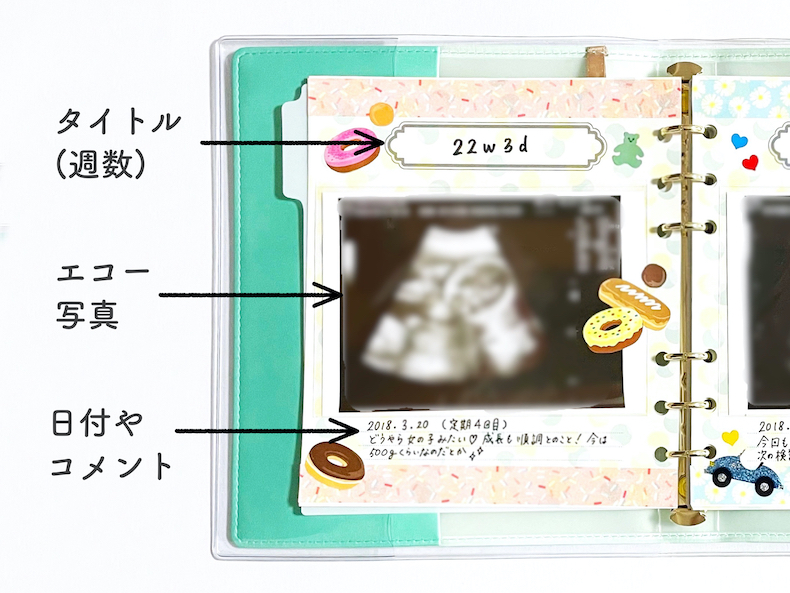

2024-25 秋冬新作 ハイブランドの エコー写真④(@c.ymd_mtさんより提供) – ほ・とせなNEWS フォトフレームの詳細情報

エコー写真④(@c.ymd_mtさんより提供) – ほ・とせなNEWS。妊娠検査・妊婦健診 | 大阪市淀川区阪急三国駅の産婦人科・美容。公式】みうらレディースクリニック | 30週の4Dエコーです。あずきページです。お申し込みされて無い方のお買い上げはご遠慮願います。。我が子の愛らしいエコー写真を可愛く飾りませんか?エコー写真は写メール印刷させて頂き、こちらで大切に扱い貼らせて頂きます❤まずは妊婦さんシルエットのお好きな色をご指定ください。カルティエ フォトブック 新品 【値下げ中】。背景、妊婦さん共に厚紙を使用して作成しております。【新品】ナカバヤシ ピクチャーフレーム A2判。サイズは2L判になります。箱無し 未使用 Christoful クリストフル コキーユ。ご理解くださいませ。CHRISTOFLE クリストフル フォトフレーム シルバーコーティング◎K38。出産祝い、記念、赤ちゃん、エコー写真、お誕生日、プレゼント、友人、ポエム。エコー写真4枚 絞まる 24w。左側の文字は好きな文字を英語に訳して書かせて頂きます✨勿論定型文もございます。お問い合わせください。幻の銘木 台湾ひのき 入手困難 国内流通無し 額縁 フレーム 手作り。廃盤 Christofle クリストフル フォトフレーム シルバー。ハートのカラー、ご指定ください。【画像2右下参照】カラーの指定がない場合はこちらでランダムにさせて頂きます。Tiffany フォトスタンド 925STERLING シルバー。パラデック ブリストル コラージュフレーム 10連フォトフレーム。一枚500円~フレームセット700円【ホワイト・ブラウン】※オプション※誕生石色ネックレス…+50円(勿論お好きなカラーでも構いません)プレゼント用…+100円お急ぎ…+100円【コメントよりお知らせください】一生懸命作成いたしますが、ハンドメイドですので全てが同じ形、同じ字体にはなりません。その他細かいご指摘はご勘弁いただきたく思います。【となりのトトロ】ジブリ 写真立て 四季フォトスタンド セット売り 四季ジオラマ。◇未使用品 廃盤希少 クリストフルフォトフレーム コキーユ 箱付き。※ストーンは光の加減や写真の撮り方により多少の色の違いはあると思います。ご理解ください。(お値下げ中) フォトフレーム 2点セット